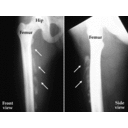

quad_contusion cause.jpg